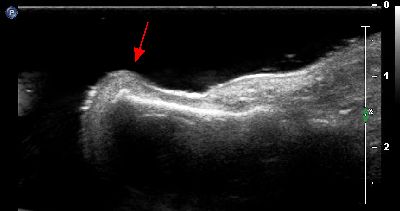

Esostosi scafoidea esostosi scafoidea